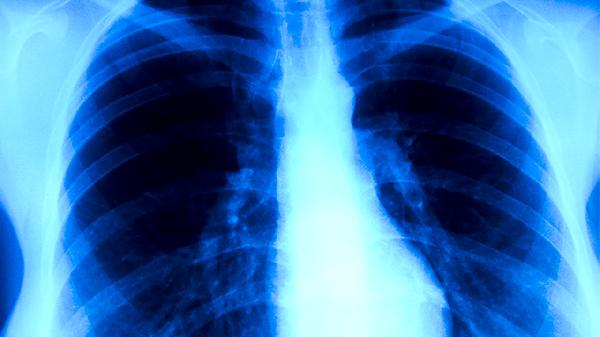

肺結(jié)核有哪些典型癥狀

肺結(jié)核的典型癥狀主要有咳嗽、咳痰、咯血、胸痛、發(fā)熱等。肺結(jié)核是由結(jié)核分枝桿菌感染引起的慢性傳染病,建議患者及時就醫(yī),積極配合醫(yī)生治療。